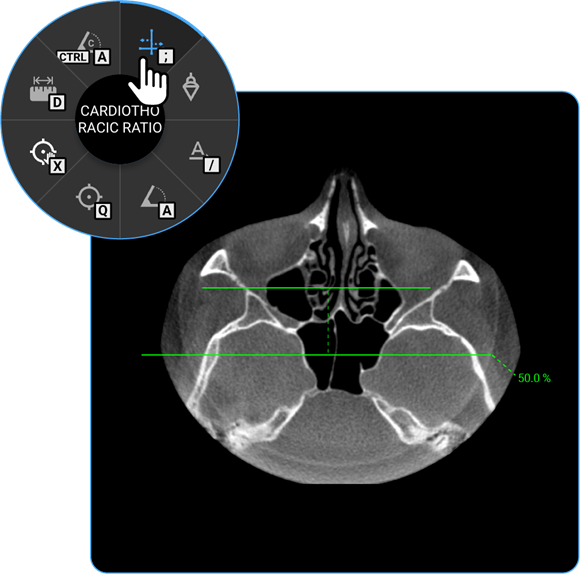

- Cardiothoracic Ratio: Click on the Cardiothoracic Ratio tool to calculate the ratio of the cardiac width to the thoracic width on chest radiographs, aiding in the evaluation of heart size.